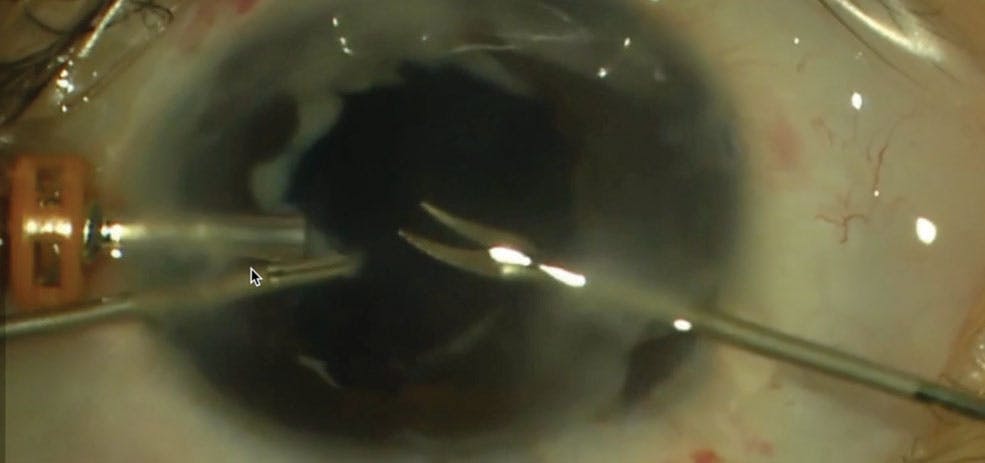

Core vitrectomy and release of the anteroposterior traction was done in the four eyes (Video 1). In one eye, the membrane encapsulating the retinal fold was also trimmed with scissors into halves without peeling (Video 2). Cohesive viscoelastic was used as an intraocular tamponade to avoid postoperative hypotony and bleeding.

Video 1. Vitrectomy in Eyes With ROP and PFV.